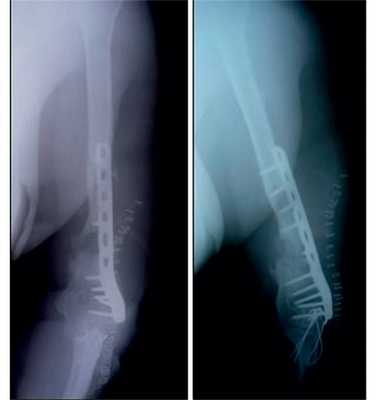

- Первый этап — пластика дефекта по Маскуле. Отломки фиксировали антеградно интрамедуллярным стержнем. Вокруг стержня на протяжении всего дефекта сформировали цементную мантию с добавлением 2 г. Ванкомицина. Мягкие ткани и рану ушили. Послеоперационный период прошёл гладко.

- Через пять недель провели второй этап лечения. Из гребня подвздошной кости взяли губчато-кортикальный аутотрансплантат 7 х 2 х 3 см. Выполнили разрез по переднему отделу плеча над плечевым суставом. Стержень удалили. Вокруг цементной мантии сформировалась биологически активная мембрана. Её аккуратно отслоили. В неё уложили аутотрансплантат, мембрану над ним ушили. Таким образом, костный дефект между отломками был заполнен губчато-кортикальным аутотрансплантатом. Отломки фиксированы пластиной LCP PHILOS. Рана ушита. Послеоперационный период прошёл без осложнений.

Пациентка наблюдалась в течение трёх лет после начала лечения. В итоге ложный сустав плечевой кости полностью сросся, аутотрансплантат перестроился и прижился.